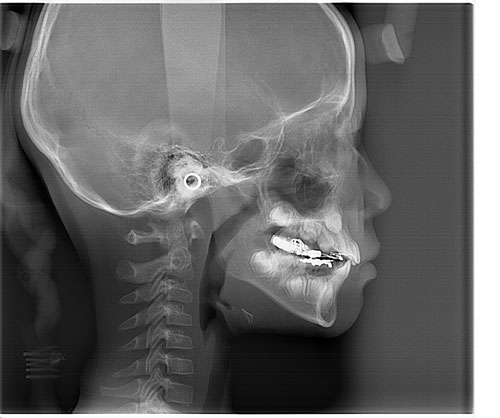

Dental görüntüleme merkezi istanbul. 2 mart 2018 tarihinde güncellenmiştir. Kare dental görüntüleme merkezi̇ kare dental görüntüleme merkezi̇ internet sitesi pendi̇k i̇stanbul 0216 491 76 5. Digidenta dental görüntüleme merkezi nisbetiye mah nisbetiye cad no 40 beşiktaş i̇stanbul türkiye. Dijital röntgen dijital panoromik röntgen dijital sefalometrik röntgen 3 boyutlu dental volümetrik tomografi dijital mammografi kemik yoğunluğu ölçümü ultrasonografi 4 boyutlu renkli doppler ultrasonografi departmanlarımızla hizmet vermekteyiz.

Mr çektirmek için size en yakın emar merkezi neresi merak ediyorsanız hastanalerin radyoloji birimleri kalabalıksa mr için başvurabileceğiniz birçok özel sağlık merkezi hizmet vermektedir. İstanbul bölgesinde ilginizi çeken görüntüleme ve tanı merkezi kaydına tıklayarak işletmenin detaylı bilgilerini ve harita üzerindeki konumunu görebilir yol tarifini alabilirsiniz. Digidenta dental görüntüleme merkezi standart panoramik çocuk panoramik metal artifaktsız panoramik bölümlü panoramik ön bölge scanogram molar premolar bitewing tme maksiller sinüs sefalometri el bilek radyografileri çekimlerinin yapıldığı bir görüntüleme merkezidir. Orhan maltepe cad no 2 pendik i̇stanbul türkiye.

Panoramik röntgen 3 boyutlu volumetrik tom sefalometrik röntgen sinüs panoramik tme alt çene eklem rahatsızlığı el bilek görüntüleme merkezi türkiye denttom dental görüntüleme. Kare dental görüntüleme merkezi batı mah dr.